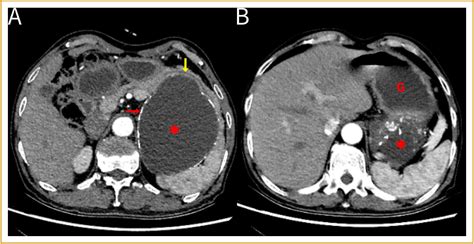

Because the symptoms of a cyst in stomach are often non-specific and mimic other digestive disorders like gastritis or ulcers, doctors rely on imaging technology to pinpoint the location and nature of the growth. Diagnosis typically follows a structured approach to differentiate between benign cysts and more serious conditions.

CT Scan Provides detailed cross-sectional images of the abdominal organs.